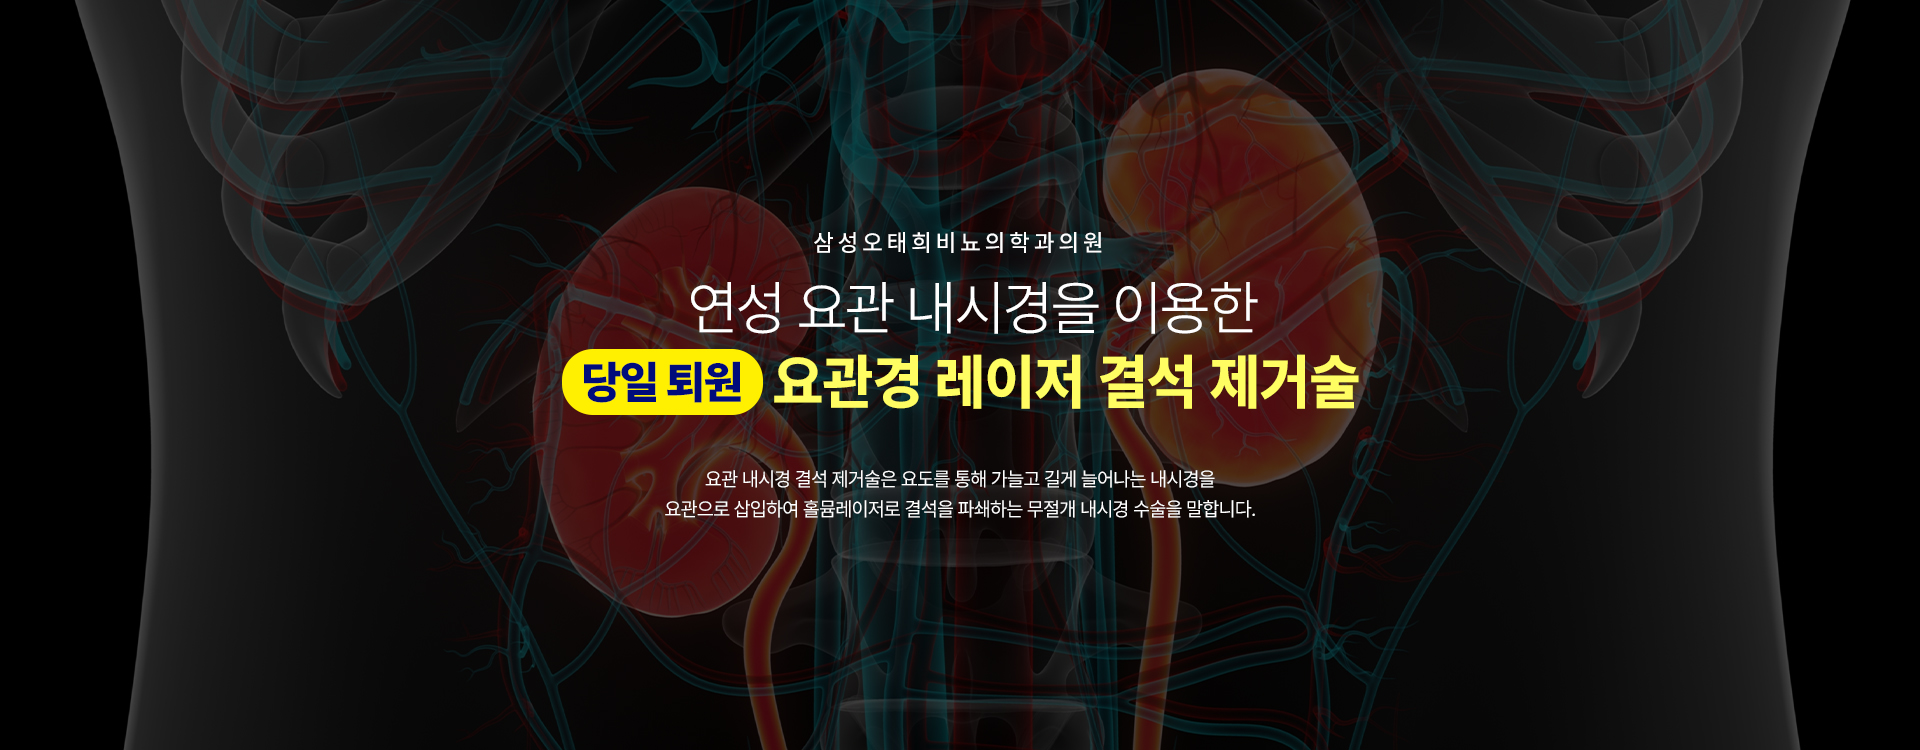

요관내시경

(경성/연성)

요관으로 삽입하여 홀뮴레이저로

결석을 파쇄하는 무절개 내시경 수술

- 요관경 레이저 결석 제거술

- 홀뮴 레이저 수술